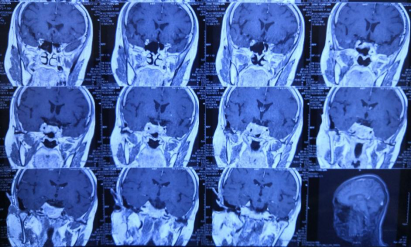

丁女士术前磁共振

丁女士术后磁共振

50岁的丁女士,1年前患阵发性头痛,10天前头疼突然加重,双眼视力下降到0.1,遂来到哈医大一院神经外科四病房求治。经核磁检查垂体病变侵犯海绵窦,包绕颈内动脉。刘利和王海洋副主任医师、殷一博主治医师会诊讨论,决定为患者行神经内镜经筛窦、蝶窦肿瘤切除术。

术中,鞍膈坍陷满意,垂体保留。刘利进一步打开海绵窦的前壁和内侧壁,直视下暴露颈内动脉,通过颈内动脉上、下和后间隙切除海绵窦内肿瘤。术后病理结果为垂体腺瘤,磁共振显示肿瘤切除较彻底,术后患者无尿崩,无垂体功能低下表现。7天后康复出院,双眼视力恢复至0.25。